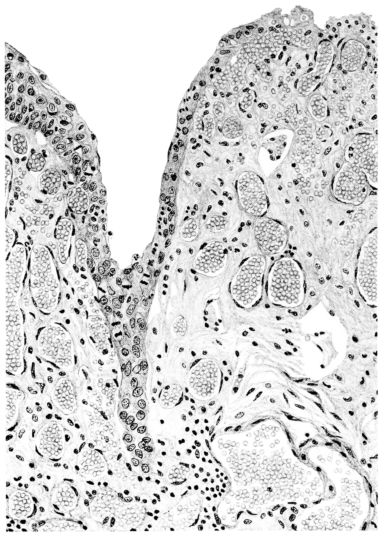

15There is considerable evidence to support the view that the disease spreads from bronchus to bronchus, and in keeping with this view, various stages in the inflammatory processes are more readily determined in these smaller structures than in the trachea. Furthermore, it must be emphasized that even the mildest and the most extreme of these stages are not infrequently encountered in the same lung. The earliest lesion is manifested by an increased homogeneity of the protoplasm of the epithelial lining of the bronchus. The cell protoplasm loses its normal granulation and the nucleus, somewhat darker than usual, becomes conspicuous on a red base (Fig. V). In the lumen of such a tube a serous exudate, perhaps mixed with mucus, is encountered, and there is some spreading apart of the surrounding muscular tissue with engorgement of the vessels. This picture merges gradually into one where the epithelium appears as a homogeneous, red-staining ribbon, devoid of nuclei, often exfoliated, in part at least, from the underlying submucosa (92). The change is traceable through the larger bronchi, even to the ducti alveolares, and not infrequently, bacteria, either as a diffuse, minute dotting or in the form of circumscribed, colony-like formations, are spread through the red, ribbon-like strand (Fig. XVI). With the exfoliation of the epithelial lining, the submucous vessels become more and more conspicuous and may bulge into the lumen of the tube (Fig. VI). That they actually weep into the lumen is proved by the presence of red blood cells in the exudate, now rich in mucus, broken-down nuclei, and desquamated cells. The necrotizing process may not extend deeper than the epithelial lining as is the status described above (140, 162), but it also frequently involves the underlying submucous and muscular layers, so that these lose their identity and stand out as homogeneous masses, in which fragmented nuclei and bacterial accumulations are prominent. Such deeper necrotizing areas may be focal (Fig. VII), or may involve the entire circumference of the tube (Fig. VIII). Occasionally, the epithelium, now dead and staining homogeneously, is lifted from the underlying submucosa in the form of a blister (66), and has very much the same appearance as the well known, early reaction which follows the application of croton oil to the rabbit’s ear. Where this occurs, the submucosa is less involved, as though the necrotizing agent had not penetrated to the same depth and the serous reaction beneath were actually a beneficent exudate. These blisters are in contrast with the deeper areas where the fibrinous mass, mixed with the dead tissue, forms an intensely staining ring or band, which extends through the bronchiolar wall even to the surrounding alveoli.

In the early stage of this process one of the most outstanding features is the absence of polynuclear leucocytes in the reactionary process, but gradually as the dead tissue sloughs away, these cells wander into the exudate and form a purulent ring, more intense in the lumen, but extending for a variable distance through the still viable wall of the structure (47) (Fig. IX). Later mononuclear cells accumulate in this wall and occur either as a diffuse mottling or as circumscribed foci in the muscle and submucous layer of the bronchiole, just as they do in the trachea. Occasionally, a striking change is found in a small bronchiole within a portion of the lung which is otherwise uninvolved by an inflammatory process. Perhaps the alveoli were the seat of a change which has subsided, but, whatever the history, the purulent mass in the bronchiole and involving its wall, stands out effectively (Fig. X).

Sooner or later, with the subsidence of the irritating agent, repair begins in the bronchus or bronchiole. If its walls have been destroyed and the lesion has extended into the surrounding alveoli to form an abscess of greater or lesser extent, or if the necrotizing process has been superficial and confined to the epithelium in large part, the reparative process is very much the same. Mitotic figures in the fibroblasts and in the endothelial cells of the capillaries abound in the young granulations (Fig. XI). However, the granulation tissue does not have an unrestricted path of growth, for if a remnant of epithelium remains, this is stimulated to grow probably in this disease as in no other. Mitotic figures are common 16and the young epithelial cells stretch across the denuded submucosa or granulation (Fig. XLVIII) and extend downward into the surrounding alveoli, not only as strands, but also as solid nests of cells (47) (Fig. XLIX). The bronchioles, therefore, show changes dependent upon the extent of the damage suffered by their walls. The vast majority, in all probability, will be restored; but if the wall has actually been necrotized, the bronchioles may be converted into small, saccular, bronchiectatic cavities (48, 110, 162) (Figs. XII and L), or obliterating bronchiolitis may result from the organization of the exudate within their lumina (82) (Fig. XI). The importance of the epithelial proliferation cannot be ignored; in many cases, it invades the surrounding lung tissue and a typical, histological picture results—an infiltrating, malignant, epithelial neoplasm (Figs. XLVIII and XLIX).